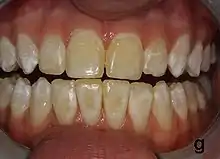

| Mild fluorosis: in its usual mildest form, fluorosis appears as opaque white patches on the enamel | |

It appears as a range of visual changes in enamel[4] causing degrees of intrinsic tooth discoloration, and, in some cases, physical damage to the teeth. The severity of the condition is dependent on the dose, duration, and age of the individual during the exposure.[1] The "very mild" (and most common) form of fluorosis, is characterized by small, opaque, "paper white” areas scattered irregularly over the tooth, covering less than 25% of the tooth surface. In the "mild" form of the disease, these mottled patches can involve up to half of the surface area of the teeth. When fluorosis is moderate, all of the surfaces of the teeth are mottled and teeth may be ground down and brown stains frequently "disfigure" the teeth. Severe fluorosis is characterized by brown discoloration and discrete or confluent pitting; brown stains are widespread and teeth often present a corroded-looking appearance.[1]

The adequate diagnosis of fluorosis can be diagnosed by visual clinical examination. This requires inspection of dry and clean tooth surfaces under a good lighting.[6] There are individual variations in clinical fluorosis manifestation which are highly dependent on the duration, timing, and dosage of fluoride exposure.There are different classifications to diagnose the severity based on the appearances. The clinical manifestation of mild dental fluorosis is mostly characterised a snow flaking appearance that lack a clear border, opaque, white spots, narrow white lines following the perikymata or patches as the opacities may coalesce with an intact, hard and smooth enamel surface on most of the teeth.[7] With increasing severity, the subsurface enamel, all along the tooth becomes more porous. Enamel may appear yellow/ brown discolouration and/ or many and pitted white-brown lesions that look like cavities. They are often described as “mottled teeth”.[8] Fluorosis does not cause discolouration to the enamel directly, as upon eruption into the mouth, affected permanent teeth are not discoloured yet. In dental enamel, fluorosis causes subsurface porosity or hypomineralizations, which extend toward the dentinal-enamel junction as the condition progresses and the affected teeth become more susceptible to staining. Due to diffusion of exogenous ions (e.g., iron and copper), stains develop into the increasingly and abnormally porous enamel.[7]